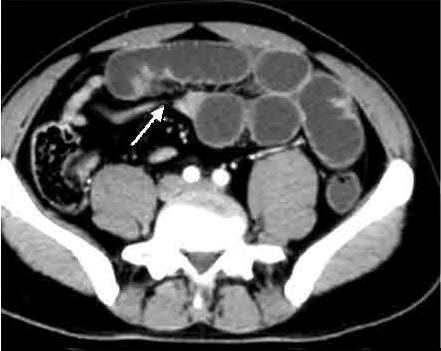

Image TDM en coupe axiale :

Signe de feces' c'est la retention de fesce dans la

portion sus -lesionelle de l'intestin ( fleche

blanche ) . |